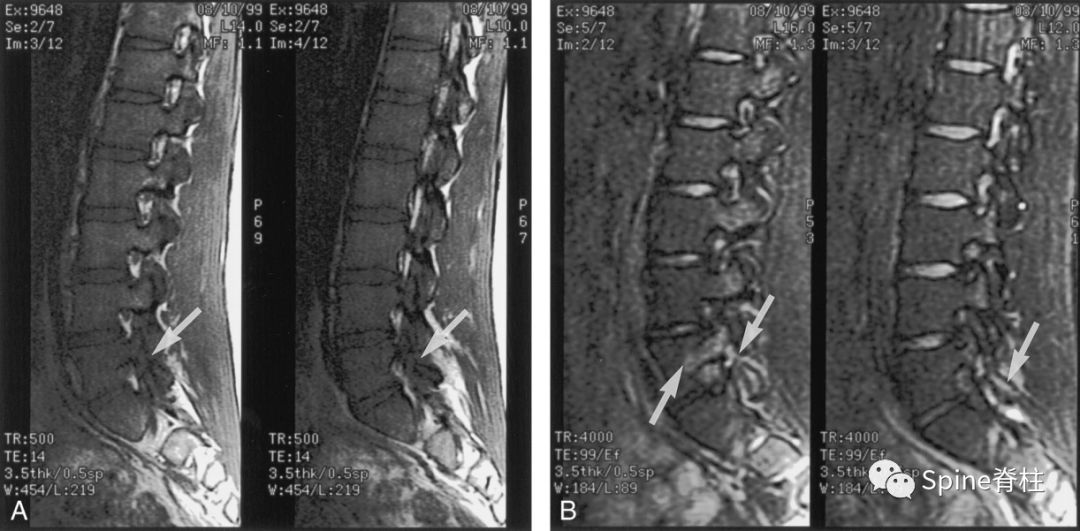

16岁的足球运动员诉右腰部疼痛。A:右侧T1加权像可见腰5峡部和椎弓根呈低信号(箭头);B:右侧T2加权像可见腰5峡部、椎弓根和关节突呈高信号(箭头)。

图:T2水肿信号且峡部皮质不连续断裂

提示L3左侧峡部裂(2级)

17岁的篮球运动员诉腰痛。A:T1像,左侧腰3峡部呈不连续的低信号(箭头);B:T2像,左侧腰3椎弓根和峡部呈高信号(箭头)

图:峡部完全断裂,断端存在明显间隙,且T2像明显水肿信号,提示L5左侧峡部裂(3级)

16岁的足球运动员,诉腰痛,以左侧为重。A:T1像可见腰5左侧峡部完全断裂(箭头);B:T2像,腰5左侧峡部、椎弓根和关节突水肿信号(箭头)

图:峡部完全断裂,但无T2水肿信号

提示为左侧L5峡部裂(4级)

13岁运动员,左侧腰骶部疼痛。A:T1像,左侧腰5峡部完全断裂(箭头);B:T2像,左侧腰5峡部清晰可见,骨质无信号改变,峡部缺损处可见轻微的高信号,提示可能为肉芽组织或积液